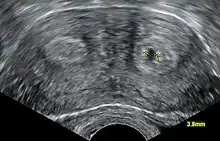

- Los dos conductos Mullerianos están fusionados pero la separación entre ellos todavía está presente, separando el sistema en dos partes. Con un septum completo la vagina, el cérvix y el útero se pueden separar. Usualmente el septum afecta solo la parte craneal del útero. Un septum uterino es la malformación uterina más común y la causa de muchos abortos espontáneos. Es diagnosticado por técnicas de imágenes médicas como ecografía o resonancias magnéticas (MRI por sus siglas en inglés). La resonancia magnética (MRI) es considerada la mejor herramienta de diagnóstico debido a sus capacidades de multiplanos así como también su habilidad de evaluar el contorno uterino, zona nodal, y otras anatomías pélvicas. Un histerosalpingograma no es considerado de utilidad debido a su inhabilidad para evaluar el contorno exterior del útero y distinguir entre un bicornio y un útero particionado.

Aparte del examen físico, el doctor necesitará tomar imágenes para determinar las características de la malformación: Ultrasonografía ginecológica, resonancia magnética (MRI) pélvica o histerosalpingografía. Un histerosalpingograma no es considerado de utilidad debido a su inhabilidad para evaluar el contorno exterior del útero y distinguir entre un bicornio y un útero particionado. Adicionalmente una laparoscopia y/o histeroscopia pueden ser recetados. En algunos pacientes el desarrollo vaginal puede ser afectado. Al contrario de lo que pudiera pensarse, esta "malformación" no representa incomodidad alguna para la persona que la presente.